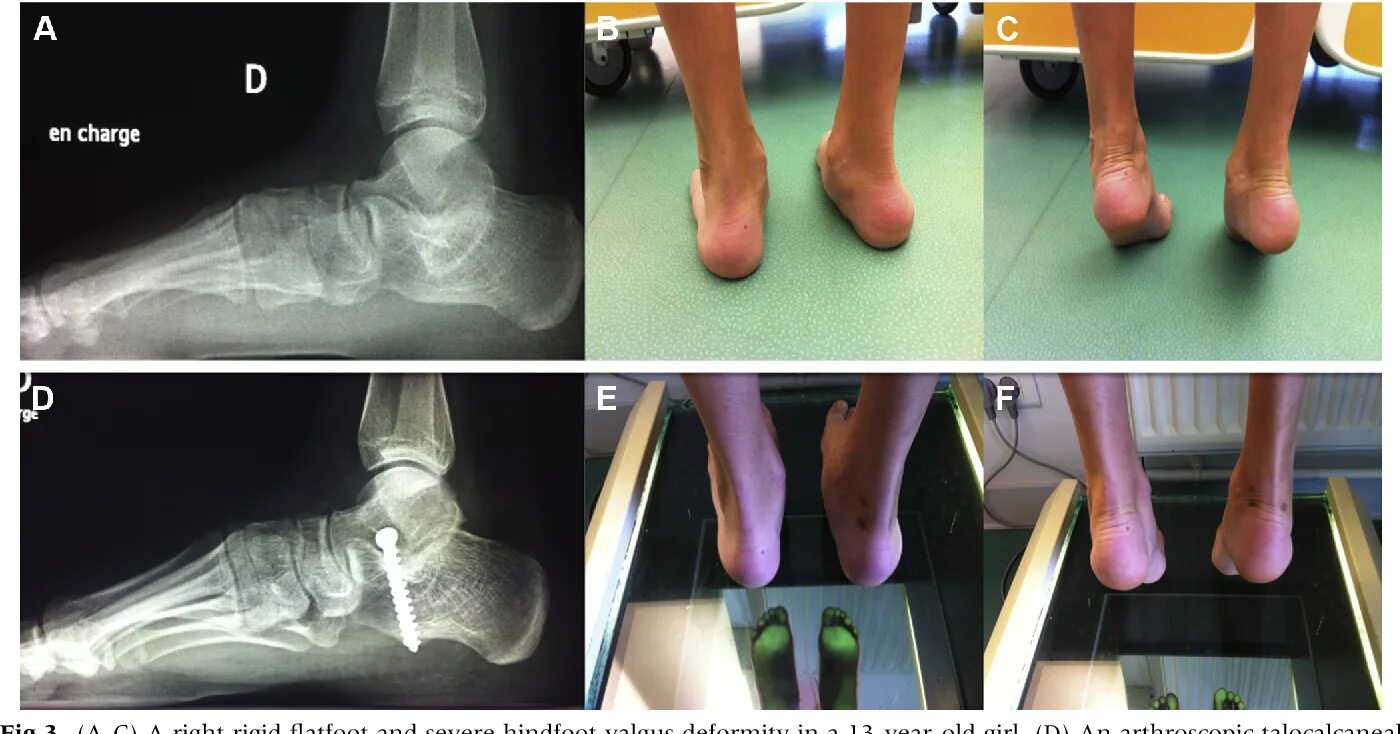

Пяточная остеотомия